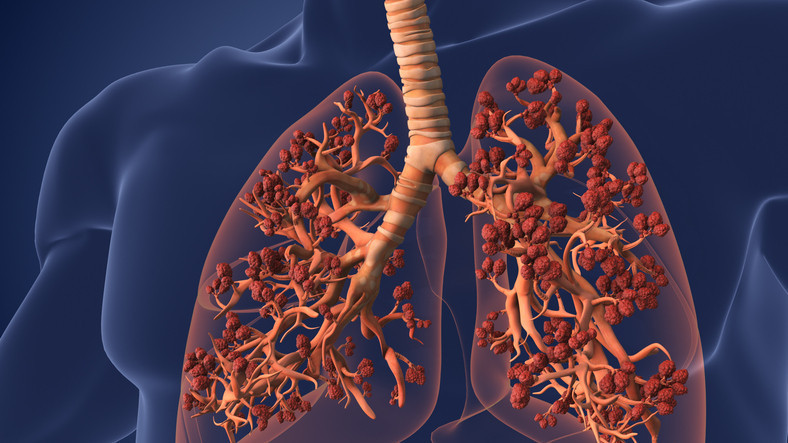

Akciğerin etrafını saran ve “plevra” olarak adlandırılan zar yapıları arasına hava kaçması sonucu akciğerin kısmen veya tamamen sönmesi durumu “pnömotoraks” olarak tanımlanıyor. Normalde akciğer ile göğüs duvarı arasında hava bulunmuyor.

Akciğerin yüzeyinden herhangi bir nedenle bu aralığa hava geçmeye başlarsa, her nefes almamızla burada biriken hava akciğere baskı yaparak, kısmen veya tamamen sönmesine neden oluyor. Akciğer sönmesinde en tipik başlangıç, ani başlayan ve tek taraflı göğüs ağrısı ile nefes darlığı oluyor.